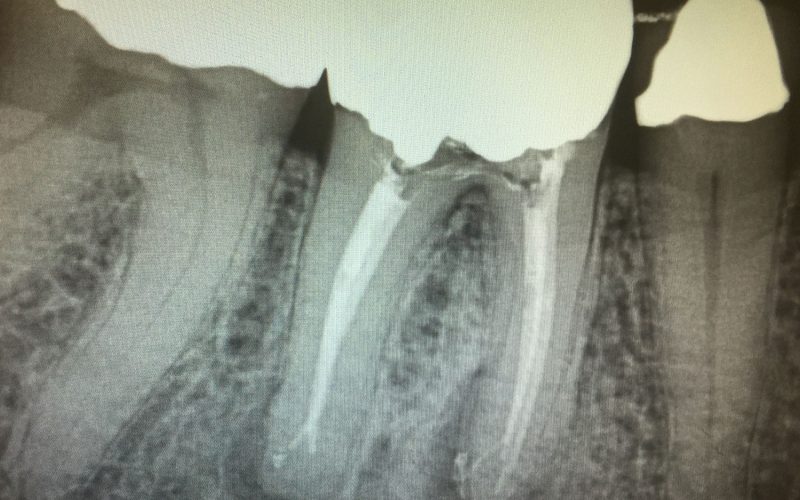

- Curved or narrow canals were not treated suitably during the initial treatment.

- Complicated canals went undetected during the initial treatment.

Once retreatment has been selected as a treatment alternative, the doctors will numb you up and regain access to the inside of your tooth. The original restorative material will be removed to enable access to the root canal. The doctors will shaped and clean the canals and microscopically examine the inside of the tooth for the presence of additional canals, contaminated tissues, or the presence of fractures. Once shaped and cleaned, the doctors will fill the canals to prevent microbes from colonizing the area and place either a temporary or a final filling.